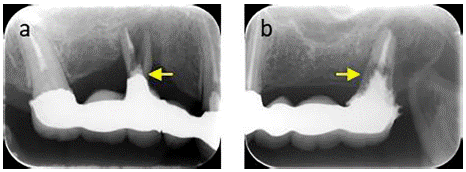

First, we repaired the detached extensive maxillary prosthesis using a self-curing resin (UNIFAST; GC Dental Co. Ltd., Tokyo, Japan) after extracting teeth 15 and 27 (Figure 2a-e).

Figure 2: Intraoral photographs and images of the maxillary prosthesis after tooth extraction. A) Frontal view. B) Maxillary occlusal view. C) Mandibular occlusal view. D) Repaired and polished maxillary. E) Intaglio surface of the repaired maxillary prosthesis.